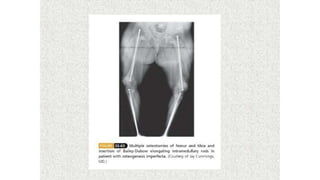

This document discusses a disease and its investigation and management. It begins by introducing Dr. Aniket Wankhede from MGIMS Sevagram and asks what the disease is. It then asks how the disease happens and discusses its causes. Next it asks how the disease appears on x-rays and describes symptoms some people experience living with it. Finally, it asks how the disease will be investigated and managed.